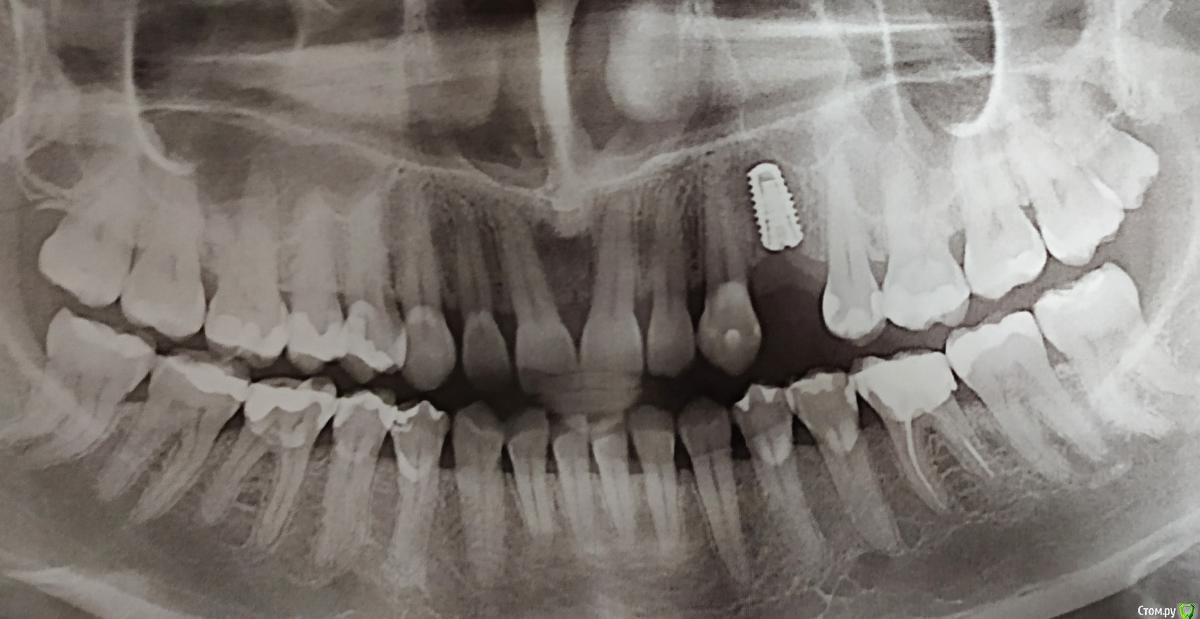

Все началось с того, что в 10 лет я поняла, что при улыбке у меня не поднимается верхняя губа и верхние зубы не видно, ну может на 1 мм. Так я ходила 20 лет с комплексом улыбки. А в 30, попав к новому стоматологу, врач предложила мне сделать художественные реставрации и удлинить верхние зубы. И тут началось.

Нельзя удлинить левый верхний, потому что нижние пошли а наклон, и он упирается в левый нижний.

Потом мне ещё удалили 4ку, и я замечталась двигать зубы, чтобы не ставить имплант. Но все отговорили, в итоге поставила имплант на днях.

3 сказала, что с прикусом все ок, вот только передние 4 немного кривые, но задвинуть их нет возможности, потому что все плотно после появления восьмерок и бонусом одной 9-ки.

Первые три врача смотрели меня без снимков.

4, посмотрев мои снимки, сказала, что на вид все просто, но если начинать просчеты, то не все так просто. И в моем случае система Invisalign лучшее решение. Она очень много всего рассказала, долго писать, но ее мнение понравилось больше всего. Проблема только в том, что капы носить два года, а у меня сейчас есть ночная от бруксизма и я постоянно на утро просипаюсь с болями в животе от того, что во рту что-то есть и сильное слюноотделение.